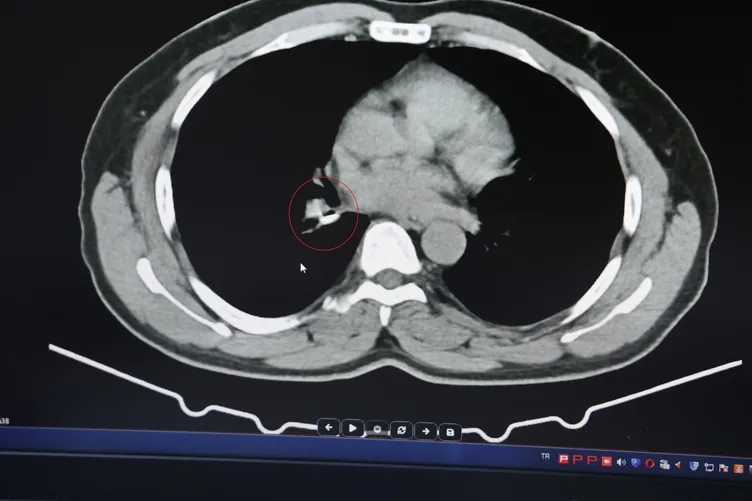

1,5 yıldır astım tanısından sonra tedaviler almaya başlayan İ.U., Prof. Dr. Abdurrahman Şenyiğit’in yanına geldiğinde yapılan tetkiklerde gerçek bambaşka çıktı. Yapılan tomografi ve bronskokopi işlemlerinde akciğere yerleşen maddenin yutulan silikon olduğu belirlendi. Silikonun çıkartılmasıyla hastanın tarifine göre şikayetlerinin ortadan kalktığı belirtildi.

Dicle Üniversitesi Tıp Fakültesi Göğüs Hastalıkları Öğretim Üyesi Prof. Dr. Abdurrahman Şenyiğit, İHA muhabirine, hastanın diş çekiminden sonra implant tedavisine gittiğini, implant tedavisinde kullanılan silikonlu diş ölçüm maddesi olduğunu ve hastada bu maddenin kullanıldığını söyledi.

Hastanın, maddenin akciğere kaçtığını hissedebildiğini fakat fark edilmediğini ifade eden Prof. Şenyiğit, o maddenin akciğerde kaldığını dile getirdi.